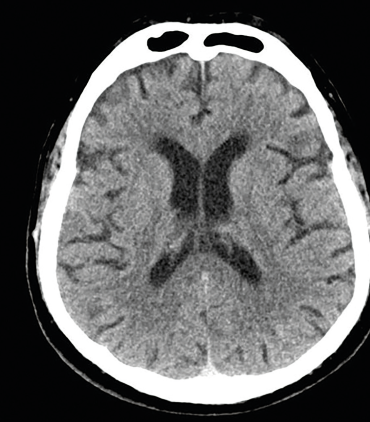

Obr. 1 CT mozku – normální nálezLéčba amaurosis fugax závisí na její příčině, nicméně vyšetření a léčba se musejí od počátku zaměřit na sekundární preventivní opatření ke snížení rizika iCMP v krátkodobém i dlouhodobém horizontu. Terapie má být zahájena okamžitě, resp. jakmile klinická, laboratorní a zobrazovací vyšetření mozku a mozkových tepen vyloučí jinou než ischemickou příčinu amaurosis fugax. Studie EXPRESS prokázala, že u pacientů po TIA došlo ke snížení 90denního rizika recidivy iCMP až o 80 %, pokud byla farmakologická léčba zahájena do 24 hodin. Medikamentózní léčba zahrnuje léčbu antitrombotickou (antiagregans u pacientů s nekardioembolickou TIA nebo antikoagulans s kardioembolizační TIA), statin a ovlivnění dalších modifikovatelných vaskulárních rizikových faktorů (arteriální hypertenze, diabetes mellitus či srdeční onemocnění). V indikovaných případech je prospěšné provedení karotické endarterektomie (CEA) nebo karotického stentingu.

Obr. 2 CT angiografie extrakraniálních a intrakraniálních tepen s významnou kalcifikovanou stenózou pravé ACI ACI – arteria carotis internaMuž, 69 let, dlouholetý kuřák, byl přijat na naše neurologické oddělení pro druhou ataku amaurosis fugax vpravo v průběhu pěti dnů. Přechodnou slepotu popisoval jako náhle vzniklý stav, při kterém měl pocit, že se mu velmi rychle vytvořila clona před pravým okem. Obě ataky prchavé monokulární amaurózy netrvaly déle než 2–3 minuty. Po druhé atace vyhledal očního lékaře, který provedl komplexní oftalmologické vyšetření včetně očního pozadí, optické koherentní tomografie a zorného pole. Nález na předním segmentu oka byl oboustranně přiměřený věku. Na očním pozadí dominovaly změny chronické hypertonické retinopatie. Zorné pole bylo v pořádku. Při přijetí na neurologické oddělení byl neurotopický nález v normě. Dle anamnézy se měl pacient léčit pro arteriální hypertenzi a hyperlipidemii, ale léky přestal užívat, protože se cítil zdráv. Při vstupním měření krevního tlaku byly zjištěny hodnoty 200/100 mm Hg. Akce srdeční byla pravidelná a vstupní elektrokardiografické vyšetření (EKG) doložilo sinusový rytmus. Fibrilace síní nebo jiná arytmie nebyly zachyceny ani při monitoraci EKG během hospitalizace na neurologické jednotce intenzivní péče (JIP). Glykemický profil byl v normě. Při vyšetření koncentrace lipidů v krvi byla zjištěna hypercholesterolemie s hodnotou LDL cholesterolu 2,94 mmol/l. Vyšetření mozku pomocí CT neprokázalo známky akutního krvácení či ischemie (obr. 1). Dle současně provedené CTA mozkových tepen byla zjištěna významná stenóza pravé ACI, nicméně hodnocení jejího stupně bylo modifikováno výraznějšími kalcifikacemi (obr. 2). Vzhledem k tomuto nálezu byla ke korelaci s CTA doplněna duplexní sonografie extrakraniálních tepen, která potvrdila 80–85% stenózu pravé ACI (obr. 3, 4). Dle transkraniální barevně kódované duplexní sonografie (TCCS) byly morfologie a hemodynamické poměry intrakraniální cirkulace v normě, nebyly zachyceny ani mikroembolické signály. V léčbě byly indikovány kyselina acetysalicylová 100 mg denně (nejprve podána nasycující dávka 300 mg) a CEA. Současně byly nasazeny atorvastatin v dávce 80 mg denně a inhibitor angiotenzin konvertujícího enzymu (ACE) v léčbě arteriální hypertenze.